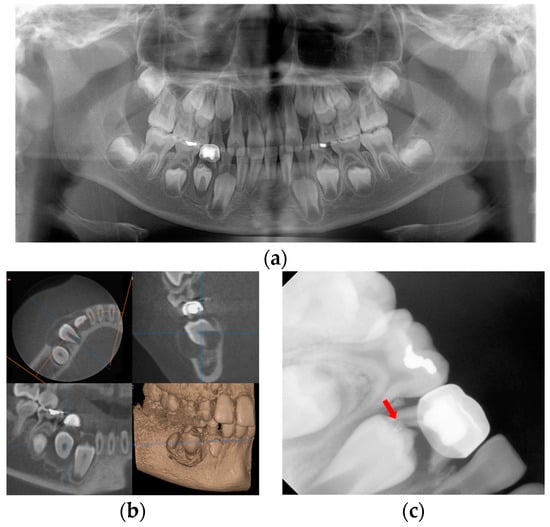

An 8-year-old boy visited the Department of Pediatric Dentistry of Kyung Hee University Dental Hospital with facial swelling on the right side of the mandible and pus discharge from the right mandibular primary first molar that had been previously treated at a local dental clinic. His medical history was unremarkable. His dental history was pulpectomy and restoration with a stainless-steel crown on the right mandibular primary first molar a year before at a local dental clinic. According to the guardian’s statement, there had been minor, painless swelling in the particular region with fluid discharge after the treatment. On dental examination, pus discharge via the right mandibular primary first molar’s disto-lingual sulcus was shown. He had poor oral hygiene and facial swelling on the right side of the mandible. Radiological examination showed a cystic lesion in the successive right mandibular first premolar region with buccal bone expansion and root resorption of the affected primary molar. In addition, a broken file was identified at the distal root tip of the affected primary molar (Figure 7).

Figure 7.

Initial visit: (a) panoramic radiograph; (b) cone-beam computed tomography; the cystic lesion around the successive right mandibular first premolar can be seen and the buccal bone swelling are observed; (c) periapical radiograph. A broken file is noted on the distal root tip of the affected primary molar (red arrow).